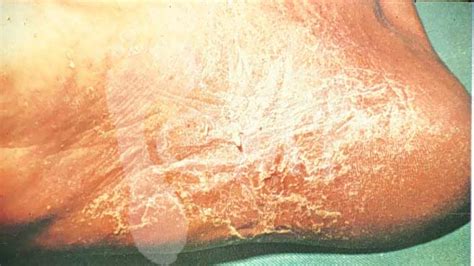

Táto forma zvyčajne začína v medziprstnom záhybe medzi tretím a štvrtým prstom a postupne sa šíri na chrbát chodidla a celé chodidlo. Vzniká pri napadnutí kože chodidla hubou T. Mentagrophytes. Prejavuje sa macerovanými (vlhkými a zmäknutými) vyrážkami na záhyboch medziprstia, obklopenými korunou šupín pozdĺž okraja. Pri progresii sa objavujú hlboké vredy, ktoré môže sprevádzať krvácanie a výtok hnisavej tekutiny.

Chronická hyperkeratická forma

Plesne nôh sa vyznačujú zhrubnutím rohovej vrstvy (hyperkeratóza) na chodidlách a bočných častiach chodidiel, čo vedie k tvorbe hustých, žltkastých alebo sivastých "hrbolčekov". K rozvoju patológie vedie infekcia hubou Trichophyton rubrum. Prejavuje sa zhrubnutou a zrohovatenou kožou, bolesťou a nepohodlím (zvýšené pri chôdzi), precitlivenosťou kože. Pri nadmernom tlaku sa na postihnutých miestach môžu objaviť praskliny a krvácajúce vredy.